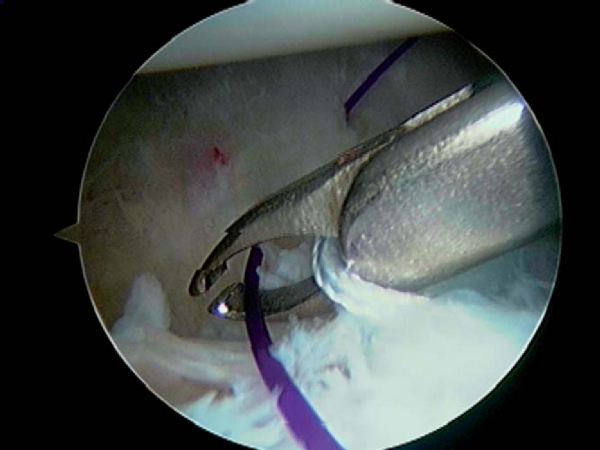

| • | A soft tissue penetrator (Spectrum suture hook, Linvatec, Largo, Fla) or crescent suture passer is passed through the labrum directly adjacent to the anchor, and the inferior FiberWire on the anchor is pulled through the labrum ( Fig. 9-3 ). |

|